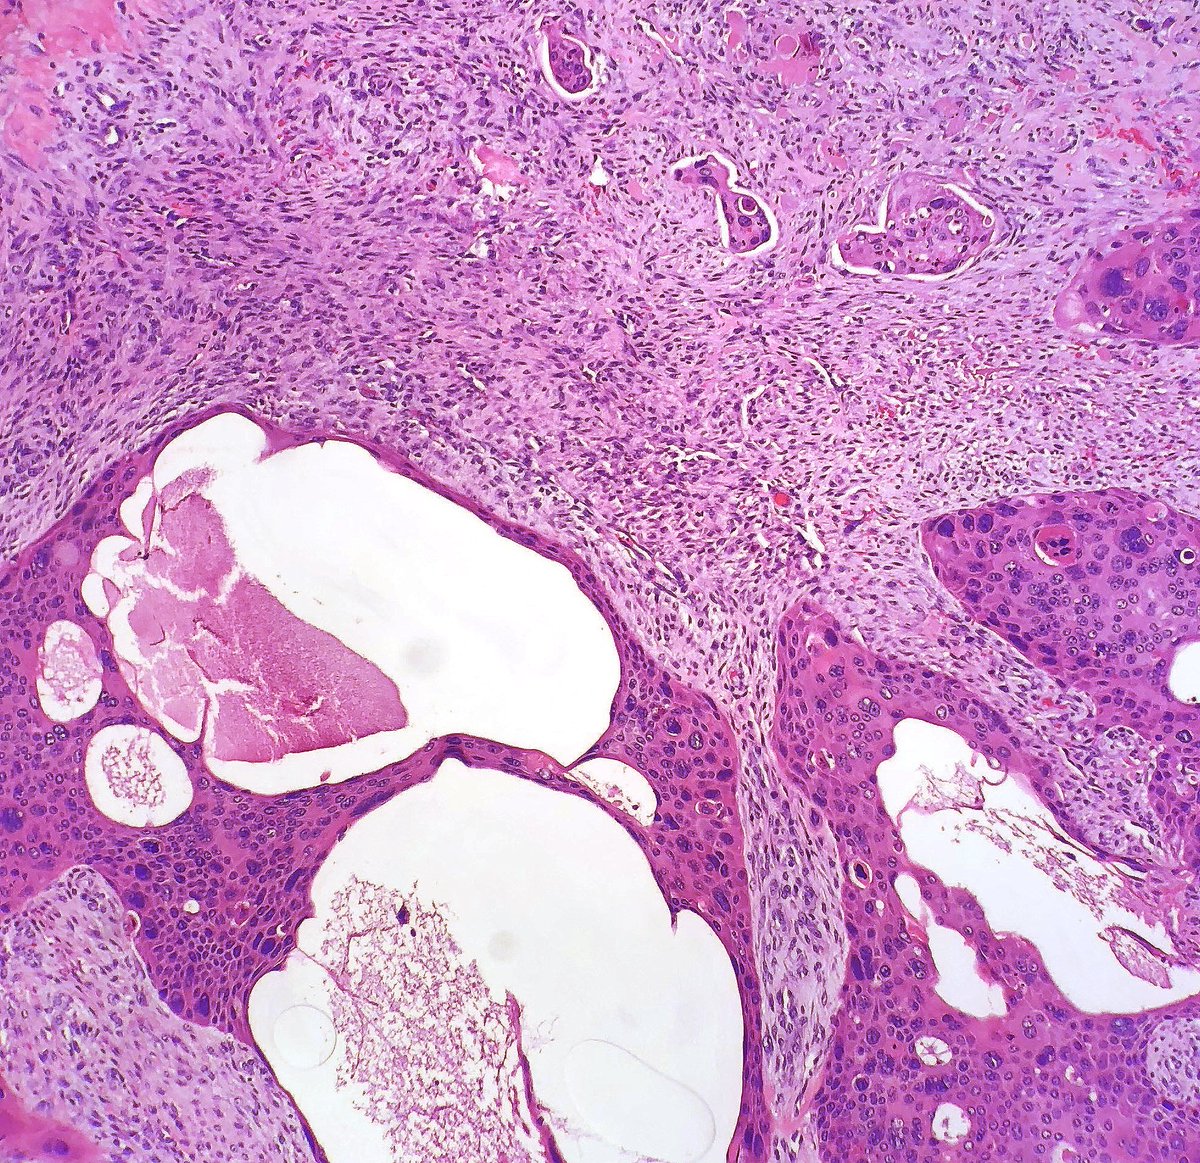

#backtobasics Pilomatrixoma 🔬 ✔️Benign skin adnexal tumor ✔️basaloid proliferation resembling the hair matrix cells, which matures into structureless eosinophilic cells lacking nuclei called shadow/ghost cells ✔️Frequently there are areas of calcification #xpath #dermpath